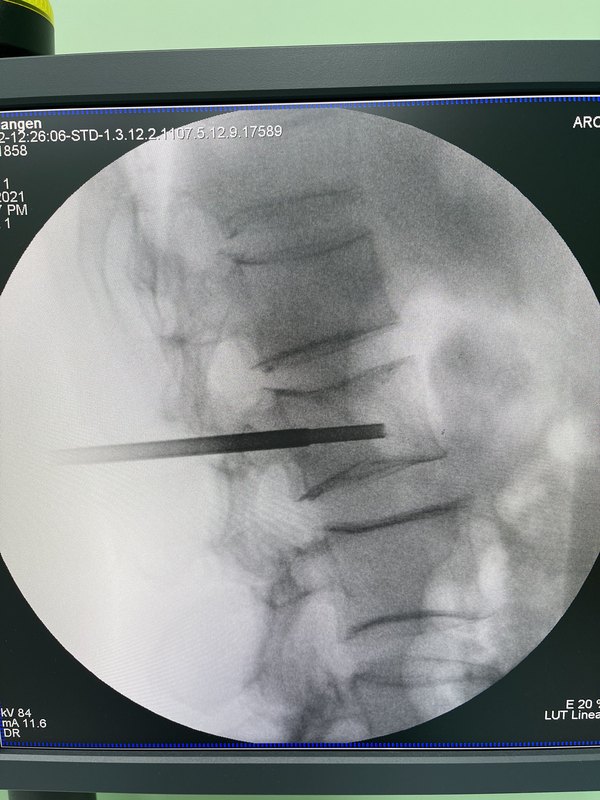

惡性腫瘤骨轉(zhuǎn)移引起的并發(fā)癥,如骨痛、病理性骨折、脊髓壓迫等嚴重影響患者生活質(zhì)量,甚至危及生命!因此,早起篩查對及早發(fā)現(xiàn)骨轉(zhuǎn)移、積極開始早期治療具有重要價值,那就需要了解骨轉(zhuǎn)移的診斷方法:X線、CT、MRI(磁共振成像)是判斷有無骨轉(zhuǎn)移的主要影像學手段。1.放射性核素骨掃描(也就是ECT),最為常用,也是懷疑骨轉(zhuǎn)移的出篩方法,具有靈敏度高、全身成像優(yōu)點,但不能顯示是成骨性改變還是溶骨性改變、不能很好的顯示骨破壞程度!2.X線片是基本的骨拍片,直觀、敏感度低;而CT是骨轉(zhuǎn)移診斷最重要的影響學方法,可以區(qū)分成骨性還是溶骨性,對骨皮質(zhì)的破壞診斷更加敏感!3.MRI對骨轉(zhuǎn)移靈敏度高,可確定病變侵襲范圍,尤其對了解有無脊髓受壓和脊柱穩(wěn)定性很關(guān)鍵!4.PET-CT(正電子發(fā)射計算機斷層顯像),可以早期發(fā)現(xiàn)骨轉(zhuǎn)移的異常征象,對乳腺癌骨轉(zhuǎn)移治療后的病情跟蹤由于ECT!總之,對骨掃描發(fā)現(xiàn)異常的患者,針對可疑病變行相應(yīng)的X線、CT和MRI檢查,確定是否存在骨破壞、破壞程度、脊髓是否受壓、脊柱穩(wěn)定性等!最后,骨活檢是查到轉(zhuǎn)移性癌細胞的診斷金標準,尤其適用于臨床可疑、臨床病情判斷不確定的骨病變!

前列腺癌是全球男性最常見的惡性腫瘤之一,隨著疾病進展,部分患者會出現(xiàn)遠處轉(zhuǎn)移,其中骨轉(zhuǎn)移是最常見的類型,約90%的晚期前列腺癌患者會經(jīng)歷這一過程[1]。骨轉(zhuǎn)移不僅會導致嚴重的骨痛,還可能引發(fā)病理性骨折、脊髓壓迫等嚴重并發(fā)癥,對患者的生活質(zhì)量和生存期產(chǎn)生重大影響。然而,得益于醫(yī)學技術(shù)的進步,前列腺癌骨轉(zhuǎn)移已不再是無解的難題。通過早期發(fā)現(xiàn)、規(guī)范化治療以及綜合管理,患者可以有效控制病情、緩解癥狀,甚至延長生存時間。一、骨轉(zhuǎn)移的“種子與土壤”:癌細胞為何偏愛骨骼?約90%的晚期前列腺癌患者會發(fā)生骨轉(zhuǎn)移。在中國,前列腺癌患者中有超過2/3在初診時已進展至中晚期階段,這類病例往往伴隨腫瘤細胞向骨骼系統(tǒng)的廣泛擴散。目前,“種子與土壤”假說為前列腺癌骨轉(zhuǎn)移的易發(fā)提供了理論依據(jù)[2]。簡單來說,骨骼微環(huán)境為癌細胞提供了“土壤”,而前列腺癌細胞則像“種子”般在此扎根生長。具體來說,前列腺癌細胞表面高表達整合素等黏附分子,使其易通過血液或淋巴系統(tǒng)擴散至骨骼,與骨基質(zhì)結(jié)合。而骨骼微環(huán)境中釋放的TGF-β、IGF-1等生長因子,刺激癌細胞增殖,為癌細胞提供了適宜的生長條件。骨轉(zhuǎn)移最常見于骨盆。作為身體承重的核心,骨盆區(qū)域血供豐富,為癌細胞的生長提供了充足的營養(yǎng),約60-70%的患者首發(fā)骨盆轉(zhuǎn)移。其次,脊柱(30%-40%)、股骨及肋骨等部位也好發(fā)骨轉(zhuǎn)移。癌細胞侵入骨骼后,可能導致骨結(jié)構(gòu)破壞?;颊咦畛醺惺艿降耐蔷植刻弁床贿m,這種疼痛常在夜間加劇并伴有體位相關(guān)性。隨著骨質(zhì)破壞程度加重,會出現(xiàn)骨痛、病理性骨折或脊髓壓迫等嚴重并發(fā)癥,導致活動受限,甚至癱瘓。二、精準偵查:揪出骨骼中的“潛伏者”由于骨轉(zhuǎn)移的早期癥狀可能不明顯,一旦出現(xiàn)夜間骨痛,彎腰困難等表現(xiàn),要引起重視。除此之外,及時進行檢測和診斷對早期篩查骨轉(zhuǎn)移顯得尤為重要。通過影像學檢查和實驗室檢查,醫(yī)生可以更早地發(fā)現(xiàn)病情并制定針對性的治療方案。1.影像學檢查(1)骨掃描(ECT):全身骨骼代謝異常的初篩工具,可顯示骨骼代謝異常區(qū)域。盡管骨掃描作為初篩手段具有重要地位,但陳舊性骨折修復灶、骨關(guān)節(jié)炎或感染區(qū)域也會出現(xiàn)顯影增強,因此還需結(jié)合其他檢查以確診。(2)MRI/CT:能清晰顯示骨質(zhì)以評估骨質(zhì)破壞細節(jié),MRI對早期轉(zhuǎn)移灶的敏感度較高,能夠較骨掃描提前3-6個月發(fā)現(xiàn)微轉(zhuǎn)移。(3)PSMAPET-CT:是一種新型精準影像學檢查手段,利用前列腺癌細胞膜表面的前列腺特異性膜抗原(PSMA)標記,可高精度定位轉(zhuǎn)移灶,將骨轉(zhuǎn)移的診斷特異性提升至92%。2.實驗室檢查(1)PSA(前列腺特異性抗原):PSA持續(xù)升高可能提示腫瘤進展,應(yīng)警惕骨轉(zhuǎn)移風險。(2)堿性磷酸酶(ALP):骨轉(zhuǎn)移活躍時,ALP水平可能升高。三、多維度治療:構(gòu)筑抗癌防線一旦確診骨轉(zhuǎn)移,患者應(yīng)盡早啟動多學科綜合治療(MDT),通過全身治療、局部治療和鎮(zhèn)痛治療的協(xié)同作用,實現(xiàn)三重防護目標:1)結(jié)構(gòu)性防護:預(yù)防病理性骨折及椎體塌陷,需結(jié)合影像學評估(如CT/MRI監(jiān)測骨穩(wěn)定性)和骨改良藥物干預(yù);2)神經(jīng)功能保全:通過早期放療或手術(shù)降低脊髓壓迫風險,避免截癱;3)疼痛控制:采用階梯鎮(zhèn)痛聯(lián)合局部治療,目標為VAS評分下降≥50%1.全身治療:控制腫瘤進展(1)內(nèi)分泌治療:作為前列腺癌骨轉(zhuǎn)移的基石,包括藥物去勢(亮丙瑞林、比卡魯胺)或手術(shù)去勢,可顯著抑制雄激素受體信號通路,降低雄激素水平延緩腫瘤進展。(2)化療與靶向治療:化療藥物(多西他賽、卡巴他賽)適用于內(nèi)分泌治療耐藥患者,可延長生存期新型靶向治療:1)PSMA靶向核素療法:如镥-177(Lu-177-PSMA)和鐳-223(Ra-223),通過精準靶向骨轉(zhuǎn)移灶釋放輻射,延長生存期并緩解骨痛,尤其適用于多發(fā)性骨轉(zhuǎn)移;2)RANKL抑制劑:地舒單抗通過阻斷RANKL/RANK通路抑制破骨細胞活性,降低骨相關(guān)事件(SREs)風險,效果優(yōu)于傳統(tǒng)雙膦酸鹽;3)納米靶向藥物:如HC&HP@TNL納米脂質(zhì)體,通過鈣磷礦化破壞腫瘤-破骨細胞偶聯(lián),早期干預(yù)骨轉(zhuǎn)移進程。2.局部治療:緩解癥狀與修復骨骼在控制腫瘤生長的同時,還需針對骨轉(zhuǎn)移的具體病灶采取局部治療,以緩解疼痛和降低并發(fā)癥風險。(1)放療:1)立體定向放療(SBRT):對孤立性骨轉(zhuǎn)移灶可實現(xiàn)高劑量精準照射,疼痛緩解率達70%-90%,且降低病理性骨折風險;2)放射性核素治療:通過全身給藥靶向骨轉(zhuǎn)移灶,對多發(fā)病灶疼痛緩解率達66.7%,且骨髓抑制風險低可快速緩解骨痛(有效率達70%),減少病理性骨折的風險。(2)骨保護劑:既往使用的雙膦酸鹽(唑來膦酸)、最近兩三年開始上市使用的地舒單抗,這兩類藥物可抑制破骨細胞活性,降低骨破壞和骨折風險,但需注意腎功能監(jiān)測及預(yù)防頜骨壞死。(3)手術(shù):若患者出現(xiàn)病理性骨折或脊髓壓迫,可能需要骨科手術(shù)干預(yù),以穩(wěn)定骨骼結(jié)構(gòu)。1)射頻/微波消融術(shù):直接滅活骨轉(zhuǎn)移灶,聯(lián)合骨水泥成形術(shù)(PVP/PKP)可快速穩(wěn)定椎體,緩解疼痛;2)三腳架螺釘技術(shù):用于骨盆轉(zhuǎn)移導致髖臼破壞時,通過導航引導植入螺釘增強穩(wěn)定性,避免關(guān)節(jié)置換。3.鎮(zhèn)痛治療骨痛是前列腺癌骨轉(zhuǎn)移患者最常見的不適癥狀之一,嚴重影響生活質(zhì)量。因此,科學合理的疼痛管理至關(guān)重要。(1)階梯用藥:根據(jù)疼痛程度選擇藥物。輕度疼痛可選擇非甾體抗炎藥(如西樂葆等);中重度疼痛可選擇阿片類藥物(如芬太尼貼劑)。(2)聯(lián)合治療:放療聯(lián)合鎮(zhèn)痛藥物,可顯著緩解頑固性骨痛。4.新輔助治療后的減瘤手術(shù)對于寡轉(zhuǎn)移的前列腺癌患者,最新的臨床研究觀點提出:如果可以嘗試進行新輔助治療后重新評估減瘤手術(shù)的可能性。這通常取決于多個因素,包括患者的具體病情、轉(zhuǎn)移的數(shù)量和位置、對新輔助治療的反應(yīng)等。實際上筆者所在的中心,也進行過為數(shù)不多的此類患者的綜合治療探索,臨床效果總體是值得肯定的。新輔助治療主要包括激素內(nèi)分泌治療、放療、化療等,旨在縮小腫瘤體積,改善生存效果。如果患者在新輔助治療后腫瘤縮小且未出現(xiàn)新的轉(zhuǎn)移病灶,可考慮進行減瘤性手術(shù)。然而最終的臨床決策,應(yīng)當由多學科團隊(泌尿外科醫(yī)生、腫瘤科醫(yī)生、放療科醫(yī)生等)共同探討,結(jié)合患者具體情況進行評估。建議患者與主管醫(yī)生詳細溝通,了解適合自己的合適治療方案。四、日常生活與隨訪管理:提高生存質(zhì)量除了醫(yī)學治療,患者的日常生活管理同樣重要??茖W的生活方式和定期隨訪,有助于提高治療效果并減少并發(fā)癥。(1)生活方式調(diào)整:1)營養(yǎng)補充:攝入充足的蛋白質(zhì)、鈣、維生素D及蔬菜水果,并適度日曬以促進骨骼健康;2)適量運動:進行步行、太極、慢跑等低強度運動,增強骨密度,減少骨折風險;3)安全措施:戒煙戒酒,避免過量飲酒,改善居家環(huán)境,避免跌倒風險。4)心態(tài)調(diào)整:積極面對疾病,配合治療,避免過度焦慮。(2)定期復查:1)低風險患者:每3個月檢查一次PSA和骨掃描,定期評估骨質(zhì)狀況,及時發(fā)現(xiàn)骨質(zhì)疏松;2)高風險患者:需縮短復查間隔,結(jié)合MRI或PET-CT進一步評估;3)監(jiān)測生化指標:定期檢查血鈣、腎功能,關(guān)注骨保護劑的副作用。五、前沿進展:未來的治療前景1.核素治療的突破近年來,核素治療在前列腺癌治療領(lǐng)域取得了顯著進展,特別是在骨轉(zhuǎn)移治療中展現(xiàn)出了獨特的優(yōu)勢。其中,放射性核素Ra-223(鐳-223)作為一種新興治療手段,受到了廣泛關(guān)注。鐳Ra-223治療骨轉(zhuǎn)移主要依賴于它的生物靶向性,其能夠模擬鈣離子與骨基質(zhì)羥基磷灰石的螯合作用,在骨轉(zhuǎn)移灶的濃聚濃度可達正常骨組織的50倍。因此,Ra-223釋放α射線靶向骨轉(zhuǎn)移病灶,在殺滅癌細胞的同時保護正常組織。臨床研究顯示,Ra-223核素放射療法可延長患者生存期,并減少骨髓抑制風險[3]。Ra-223常與內(nèi)分泌治療聯(lián)用,為多發(fā)性骨轉(zhuǎn)移患者提供了新的治療選擇。最近,放射性核素錒-225(Ac-225)因其在癌癥靶向α治療(TAT)中的卓越表現(xiàn)成為核醫(yī)學領(lǐng)域的最新明星,但是,因為其極復雜的生產(chǎn)制造工藝要求,全球的供應(yīng)量僅夠滿足極少數(shù)患者,2023年全球產(chǎn)量僅夠1000名患者使用。國內(nèi)僅中國原子能科學研究院(CIAE)具備百兆電子伏級回旋加速器,有能力生產(chǎn)錒-225。隨著國內(nèi)企業(yè)(如東誠藥業(yè)、中國同輻)加速布局核藥全產(chǎn)業(yè)鏈,Ac-225的國產(chǎn)化進程有望提速。然而,臨床轉(zhuǎn)化仍需跨過三大門檻:1)放射性藥物穩(wěn)定性:優(yōu)化螯合劑-核素結(jié)合力,減少子核素(如213Bi)泄露導致的腎毒性;2)靶向遞送效率:開發(fā)新型抗體/多肽載體,提升腫瘤組織攝取率;3)政策支持:推動醫(yī)用同位素生產(chǎn)納入國家重大科技專項,降低審批與采購壁壘。2.殼聚糖納米凝膠藥物遞送同仁醫(yī)院泌尿外科劉敏教授,聯(lián)合東華大學生物工程學院史向陽教授、曹雪雁副研究員,攻堅克難,針對晚期前列腺癌的骨相關(guān)事件,為了克服傳統(tǒng)多西他賽化療的毒副作用,針對核因子κB受體激活劑(RANK)/RANK配體(RANKL)信號通路進行靶向遞送研究,研發(fā)了一種仿生聚吡咯殼聚糖納米凝膠[4]。該復合納米凝膠不僅能夠靶向遞送化療藥物多西他賽至前列腺癌細胞,實現(xiàn)前列腺癌模型的靶向化療,以此減輕多西他賽對其他器官造成的毒性效應(yīng);同時還能夠遞送小干擾RNA(Si-RNA-RANK)沉默RNA的表達,以干預(yù)RANK/RANKL信號通路,抑制前列腺癌細胞的骨轉(zhuǎn)移。該仿生納米遞送系統(tǒng)聯(lián)合化療和基因治療精準靶向,并高效抑制前列腺癌原發(fā)腫瘤生長,同時從基因?qū)用孀柚骨傲邢侔┘毎墓寝D(zhuǎn)移,為前列腺癌骨轉(zhuǎn)移的治療提供了全新的治療策略研究方向。六、結(jié)語骨轉(zhuǎn)移作為前列腺癌晚期常見的轉(zhuǎn)移形式,雖然給患者帶來了巨大挑戰(zhàn),但通過早期發(fā)現(xiàn)、合理隨訪和多學科協(xié)作的個體化治療,仍可有效緩解癥狀、提高生活質(zhì)量并延長生存期?;颊邞?yīng)保持積極心態(tài),配合治療,同時注重健康生活方式的調(diào)整,專注于改善自身健康狀況與生活質(zhì)量。若出現(xiàn)骨痛或活動受限,應(yīng)及時就醫(yī),制定個體化治療方案,以提高生存率和生活質(zhì)量。?參考文獻1.GuoX,LiS.Bonemetastasesofprostatecancer:Molecularmechanisms,targeteddiagnosisandtargetedtherapy(Review).OncolRep.2025;53(4):46.doi:10.3892/or.2025.88792.YinJJ,PollockCB,KellyK.Mechanismsofcancermetastasistothebone.CellRes.2005;15(1):57-62.doi:10.1038/sj.cr.72902663.CelestiaS.Higanoetal.,Clinicaloutcomesandpatient(pt)profilesinREASSURE:Anobservationalstudyofradium-223(Ra-223)inmetastaticcastration-resistantprostatecancer(mCRPC).JCO38,32-32(2020).DOI:10.1200/JCO.2020.38.6_suppl.324.?YuQ,GaoY,DaiW,etal.CellMembrane-CamouflagedChitosan-PolypyrroleNanogelsCo-DeliverDrugandGeneforTargetedChemotherapyandBoneMetastasisInhibitionofProstateCancer.AdvHealthcMater.2024;13(20):e2400114.doi:10.1002/adhm.202400114